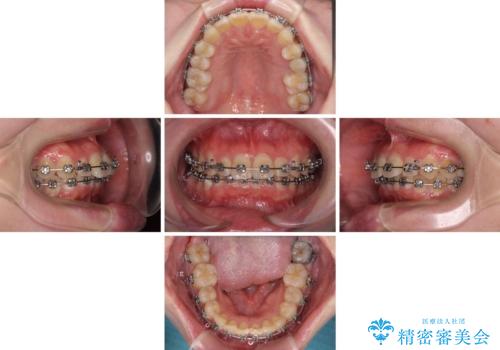

- メタルブラケット

- 1年7ヶ月

- デコボコの歯列が気になるとことで来院された患者様です。

歯列不正としては軽度であったため、インビザラインでもワイヤー装置でも対応可能でしたが、ご本人の希望によりインビザラインによる矯正治療を行うこととしました。

マウスピース矯正は、自己管理が非常に重要と事前にお伝えしておりましたが、毎日のマウスピース装着が遵守できず、ワイヤー装置での矯正治療へ変更することとなりました。

インビザラインからワイヤー装置へ変更すると、費用が追加となるため、ワイヤー装置は目立つものの費用を抑えることのできるメタルブラケットを使用しました。